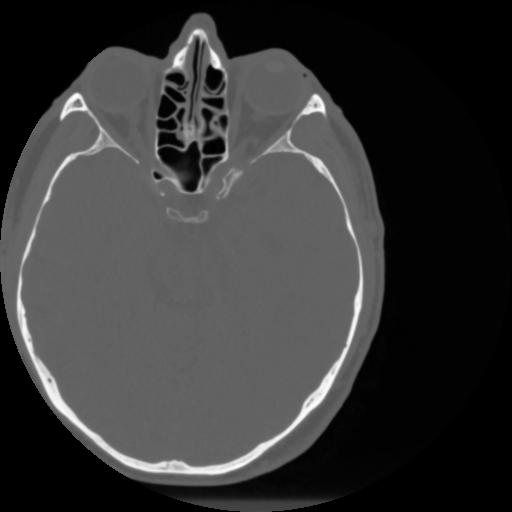

4 CEREBRO,,Vol,0.5,CEREBRO,,